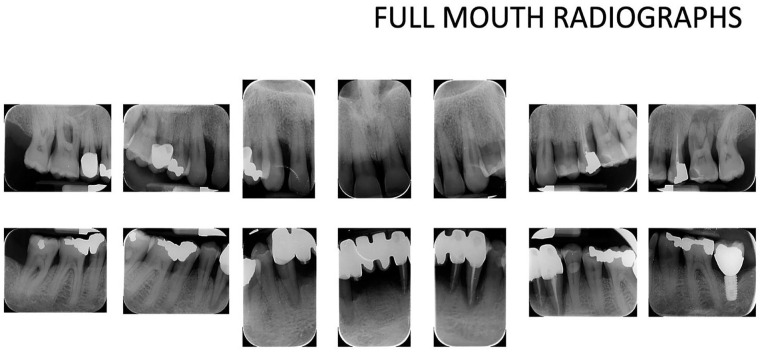

年龄相关性黄斑变性(AMD)是50岁及以上人群视力受损的主要原因,主要影响中央视力。本研究旨在调查牙周病与年龄相关性黄斑病变之间的潜在关联。66岁男性受试者,患有年龄相关性退行性黄斑病变和严重牙周病,评估和治疗。在最初阶段的非手术牙周治疗后,重新评估牙周指标。此外,还进行了用种植体代替无希望牙的拔牙。视网膜地形图用于评估可能的病理消退,并给予适当的抗vegf治疗。结果显示牙周病的消退和退行性黄斑病变的改善。这些初步结果即使令人鼓舞,也应该得到更大规模前瞻性试验的支持。

Age-related macular degeneration (AMD) is a leading cause of significant vision impairment in individuals aged 50 and older, primarily impacting central vision. This study seeks to investigate potential associations between periodontal disease and age-related maculopathy in the analyzed clinical case. A male subject of 66 years old, with age-related degenerative maculopathy and severe periodontal disease, was evaluated and treated. After an initial phase of non-surgical causal periodontal therapy, the periodontal indices were re-evaluated. In addition, the extraction of hopeless teeth replaced by dental implants was performed. A retinal topography was used to assess possible regression of the pathology, and proper anti-VEGF therapy was administered. The results showed a regression of periodontal disease and an improvement of the degenerative maculopathy. These preliminary results, even if encouraging, should be supported by larger prospective trials.